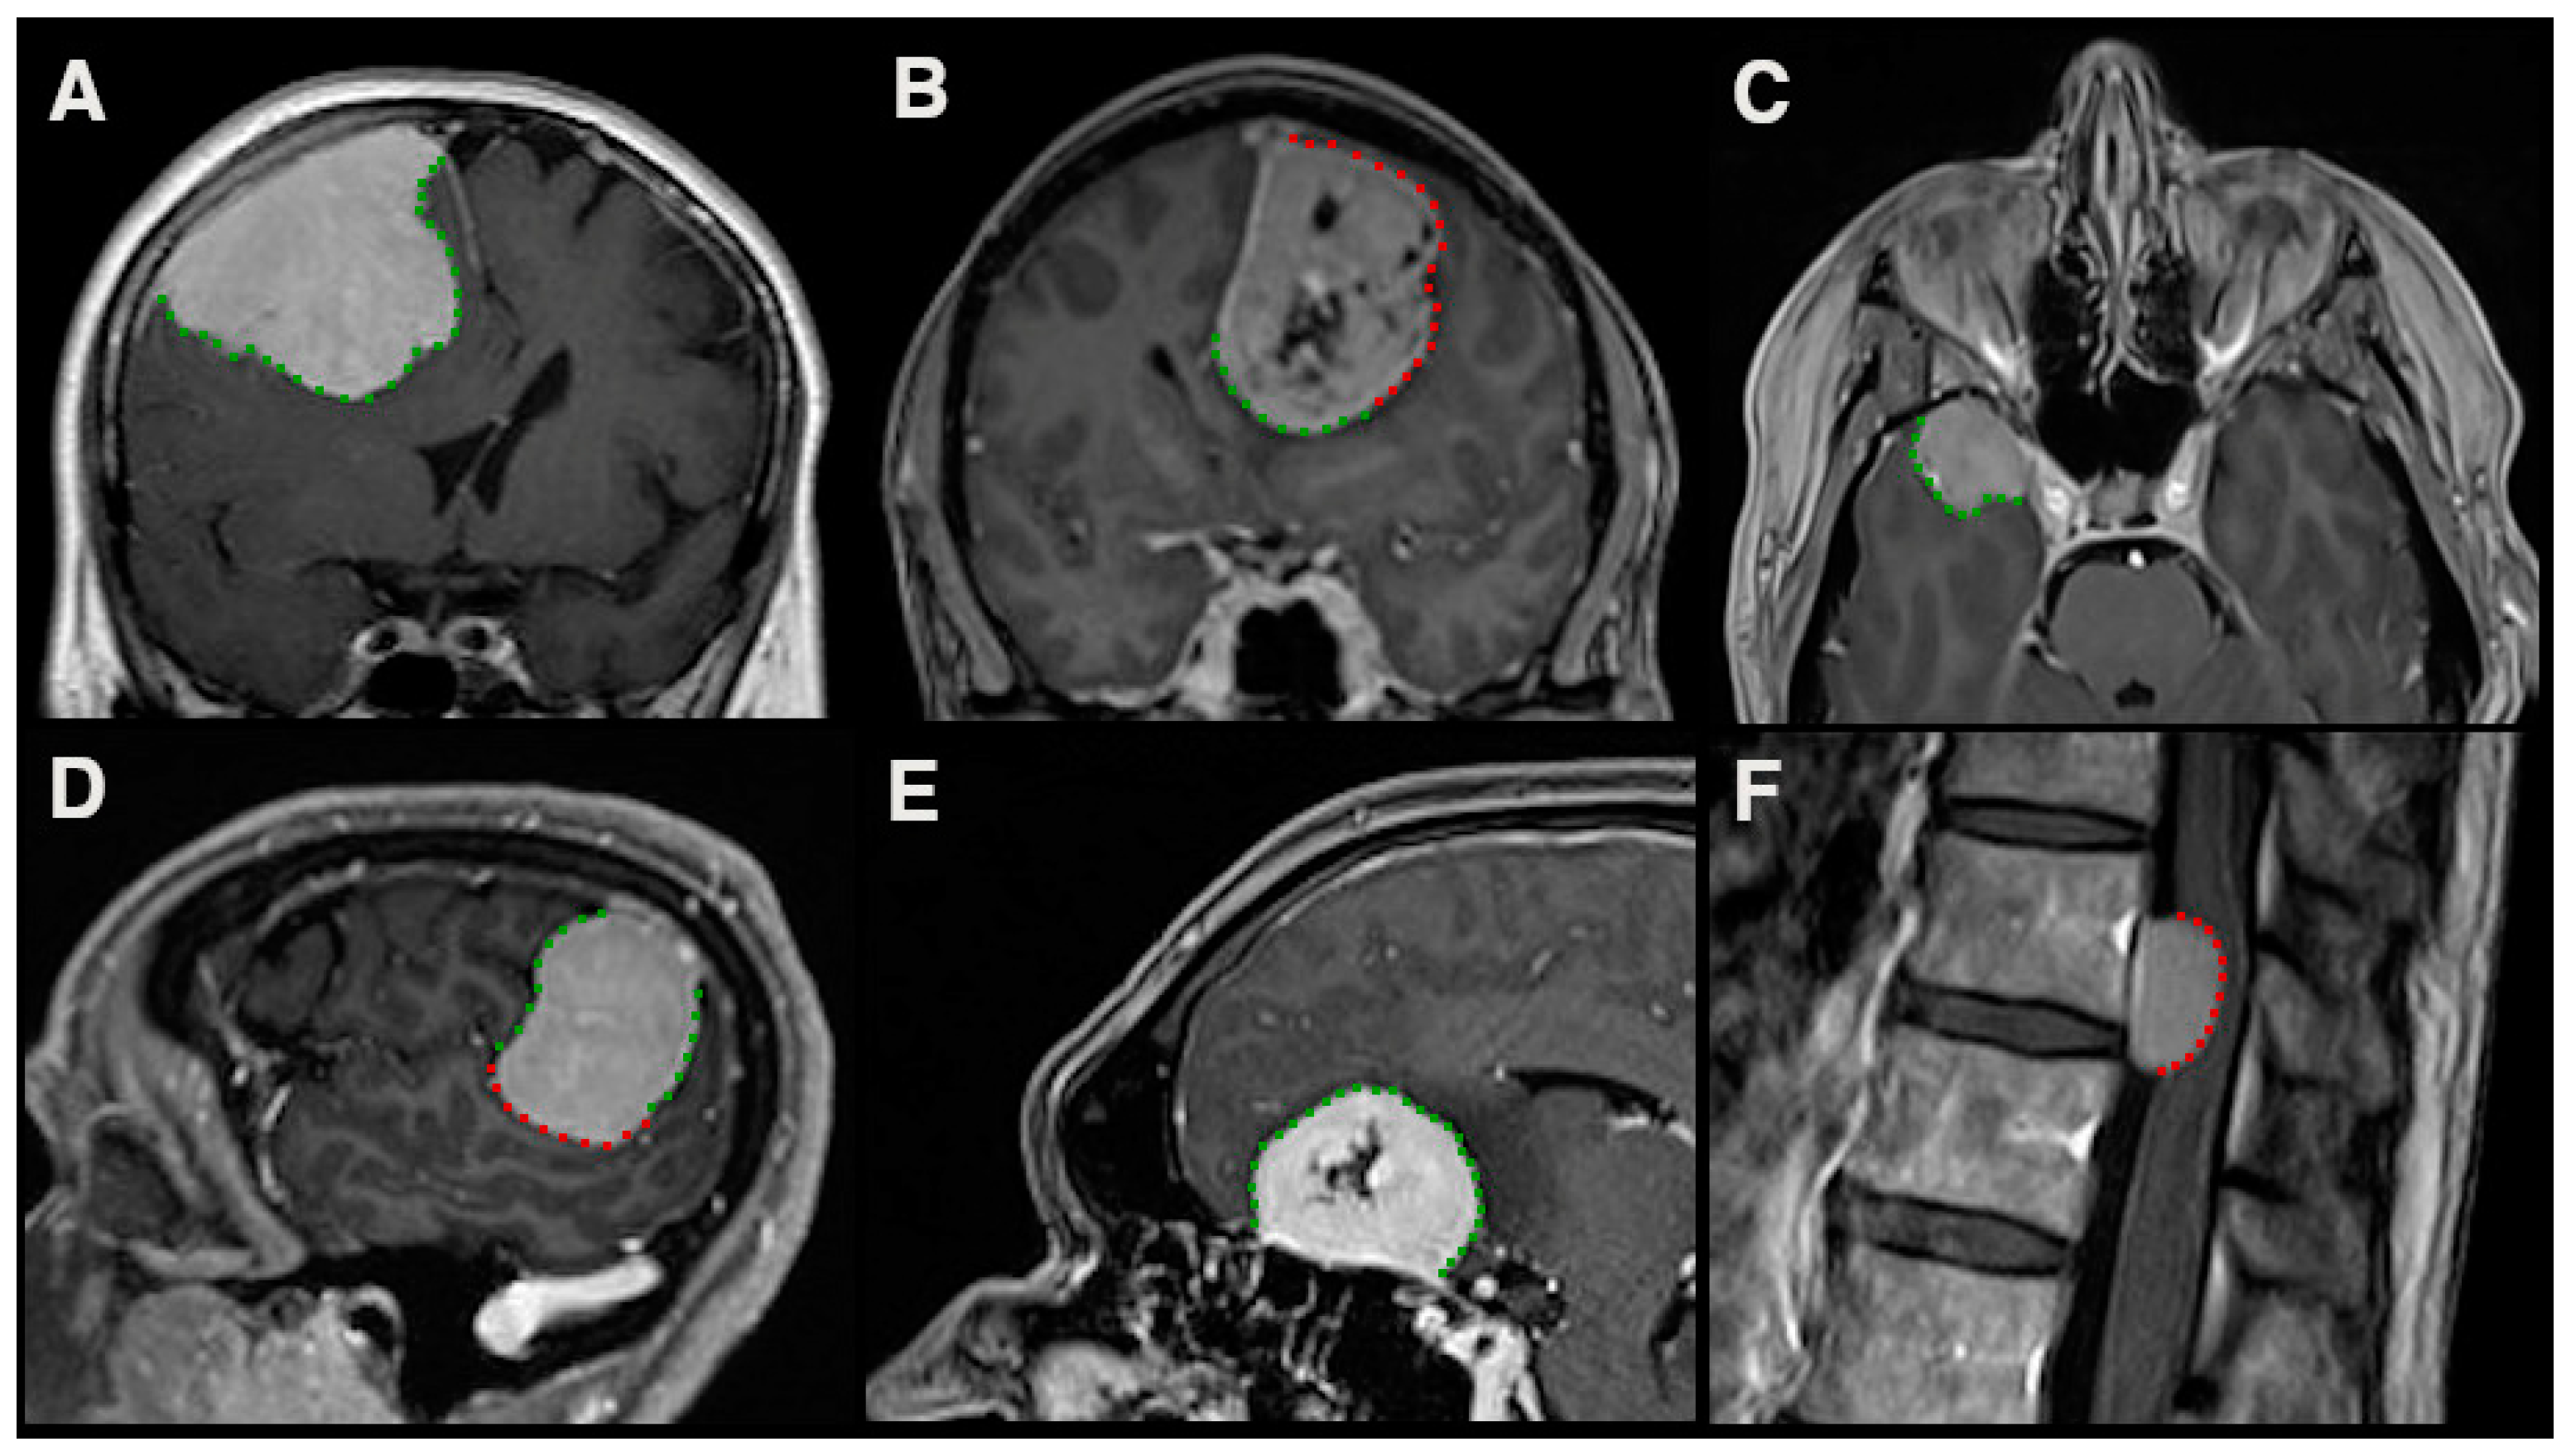

3. Imaging Aspects of Invasive Growth

- Adeli, A.; Hess, K.; Mawrin, C.; Streckert, E.M.S.; Stummer, W.; Paulus, W.; Kemmling, A.; Holling, M.; Heindel, W.; Schmidt, R.; et al. Prediction of brain invasion in patients with meningiomas using preoperative magnetic resonance imaging. Oncotarget 2018, 9, 35974–35982. [Google Scholar] [CrossRef] [Green Version]

- Joo, L.; Park, J.E.; Park, S.Y.; Nam, S.J.; Kim, Y.H.; Kim, J.H.; Kim, H.S. Extensive peritumoral edema and brain-to-tumor interface MRI features enable prediction of brain invasion in meningioma: Development and validation. Neuro Oncol. 2021, 23, 324–333. [Google Scholar] [CrossRef] [PubMed]

- Ong, T.; Bharatha, A.; Alsufayan, R.; Das, S.; Lin, A.W. MRI predictors for brain invasion in meningiomas. Neuroradiol. J. 2021, 34, 3–7. [Google Scholar] [CrossRef]

- Ko, C.C.; Zhang, Y.; Chen, J.H.; Chang, K.T.; Chen, T.Y.; Lim, S.W.; Wu, T.C.; Su, M.Y. Pre-operative MRI Radiomics for the Prediction of Progression and Recurrence in Meningiomas. Front. Neurol. 2021, 12, 636235. [Google Scholar] [CrossRef]

- Kandemirli, S.G.; Chopra, S.; Priya, S.; Ward, C.; Locke, T.; Soni, N.; Srivastava, S.; Jones, K.; Bathla, G. Presurgical detection of brain invasion status in meningiomas based on first-order histogram based texture analysis of contrast enhanced imaging. Clin. Neurol. Neurosurg. 2020, 198, 106205. [Google Scholar] [CrossRef] [PubMed]

- Behling, F.; Fodi, C.; Gepfner-Tuma, I.; Machetanz, K.; Renovanz, M.; Skardelly, M.; Bornemann, A.; Honegger, J.; Tabatabai, G.; Tatagiba, M.; et al. CNS Invasion in Meningioma-How the Intraoperative Assessment Can Improve the Prognostic Evaluation of Tumor Recurrence. Cancers 2020, 12, 3620. [Google Scholar] [CrossRef] [PubMed]